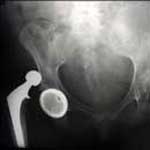

Hip replacement surgery is a treatment for severe hip arthritis. Most patients understand that hip replacements can wear out over time, but exactly how long is a hip replacement supposed to last?

Unfortunately, an artificial hip is not as durable as your own hip. Because the hip replacement implants are made of metal and plastic, these materials begin to wear over time, just like the rubber on your car tires. Even hip replacements made with special materials designed to last a long time do not last forever.

The good news is that studies show that common types of hip replacements can last more than 20 years. While there are hundreds of studies, they all vary in the type of implant used and the type of patient who had their hip replaced. One very large study found that 80% of hip replacements were functioning well after 15 years in the younger (less than 65) patients, and 94% of the older (over 65) patients.